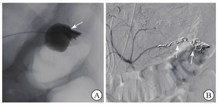

患者生命体征平稳,入院后未再次便血,暂予禁食水、补液、抑酸处理,给予200 mL氨甲环酸氯化钠注射液止血、2 U悬浮红细胞输注。2020年11月1日9:00复查血红蛋白为66 g/L,生命体征平稳,无便血,继续给予内科保守治疗并观察。11月2日4:22患者排大量(约500 mL)鲜血便,伴意识模糊,血压为57/35 mmHg,急查血常规示红细胞计数为0.85×109/L,血红蛋白为26 g/L,平均红细胞体积为93 fL,平均红细胞血红蛋白含量为30 pg,平均红细胞血红蛋白浓度为329 g/L。11月2日8:22急诊行第1次结肠镜检查,在直肠下段可见溃疡糜烂面,边界清楚,有黄苔附着,表面见大小约3.0 cm×2.5 cm的陈旧血块,未见明显活动性出血;进镜至回盲部观察3 min,未见血液从小肠流出;退镜过程中可见结肠腔内大量血凝块,反复冲洗未见新鲜出血(图2)。肠镜退出后20 min,患者再次排出大量(约500 mL)鲜血便,伴意识丧失。给予患者双通道加压补液、血管活性药物泵入、4 U悬浮红细胞输注、400 mL新鲜冰冻血浆输注后,收缩压上升至60~90 mmHg,意识稍有恢复。11月2日11:02急诊行全腹部+盆腔增强CT检查,动脉期、门脉期扫描示胰尾部与结肠间类圆形病灶明显强化,程度均与动脉相近,最大密度投影重建图像示病灶与脾动脉、结肠脾曲相连(图3A);延迟期扫描示结肠脾曲左侧肠腔内可见密度增高,提示肠腔内对比剂进入(图3B)。考虑脾动脉瘤破裂致结肠脾曲活动性出血。11月2日13:35行第2次结肠镜检查,进镜至结肠脾曲,可见黏膜隆起伴充血肿胀,顶端可见糜烂,有白色血栓头附着,未见活动性出血,以肠镜触碰血栓头可见鲜红色血液喷出(图4A);予以钛夹夹闭出血动脉,夹闭过程中可见大量活动性出血,6枚钛夹夹闭后暂无活动性出血(图4B)。结肠镜下止血后,患者仍持续排出少量血便(约80 mL/h),收缩压为80~100 mmHg。考虑动脉瘤破裂致结肠脾曲出血,钛夹止血不彻底,病因不能去除,仍有出血可能,遂于11月2日15:05行数字减影血管造影(digital subtraction angiography,DSA),可见脾动脉瘤样扩张,最大径为4.2 cm(图5A),证实为脾动脉真性动脉瘤,但未发现对比剂大量外渗,考虑因患者血压较低暂未出血或内镜下钛夹成功止血;在瘤体左侧可见结肠腔内的钛夹,证明存在脾动脉瘤结肠脾曲瘘。采用介入导管超选至脾动脉,置入6枚弹簧圈栓塞,再次造影未见对比剂溢出,动脉瘤不再显影(图5B)。11月3日患者排出少量血便,但生命体征平稳。术后1周复查增强CT示脾动脉栓塞术后,脾动脉瘤腔内未见对比剂进入,肠腔未见活动性出血。术后2周患者无便血、腹痛等不适,恢复进食后粪便常规和隐血试验均阴性,复查血红蛋白为97 g/L,康复出院。随访1.5年,患者未再便血,血红蛋白、血小板计数均在正常参考值范围内,粪便常规检查未见异常。